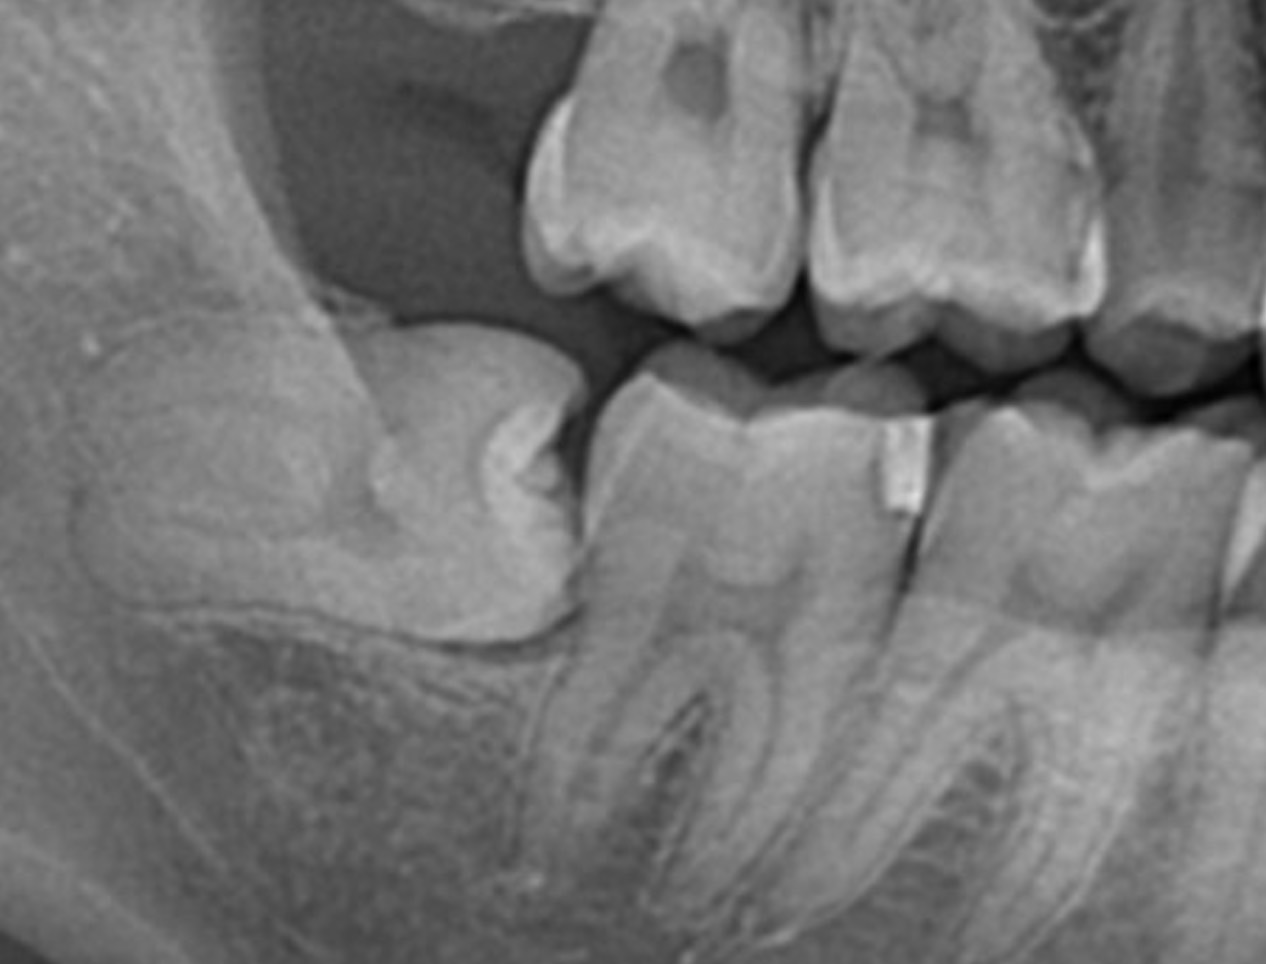

レントゲン画像

主訴として「食事をしてたら右下の奥歯が欠けて沁みる」とのことでした。

今回治療の歯は「右下7」なので、画像の横向きになった親知らずの隣の歯となります。